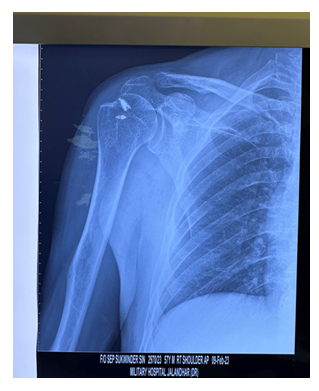

A total of 63 cases were undertaken for Arthroscopic assisted Mini Open Repair using Acromial split. 42 cases were followed up for an average of 12 months (range 6 – 24 months) and unfortunately rest were lost to follow up. 26 males (62%) and 16 females (38%) were operated for various rotator cuff pathologies which were confirmed by MRI and X ray and were followed up with Constant scores being recorded. The advantage of this technique is that it is versatile and dynamic and all consecutive patients with rotator cuff tears were included in this study design (Table 1). The average age of patients was 52 in this study.